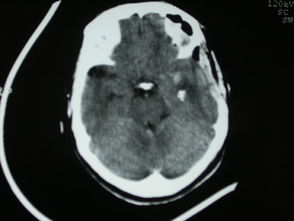

腦積水主要是由于顱腦內(nèi)出現(xiàn)了各種病變或者是疾病性使腦脊液分泌的情況過多,存在了吸收障礙性的情況下,就會(huì)導(dǎo)致顱內(nèi)腦脊液量出現(xiàn)增加的情況,而慢慢使腦室系統(tǒng)出現(xiàn)擴(kuò)大或者是蛛網(wǎng)膜下腔位置處有擴(kuò)大的一個(gè)癥狀性,是會(huì)導(dǎo)致各種身體出現(xiàn)連鎖方面的癥狀性。